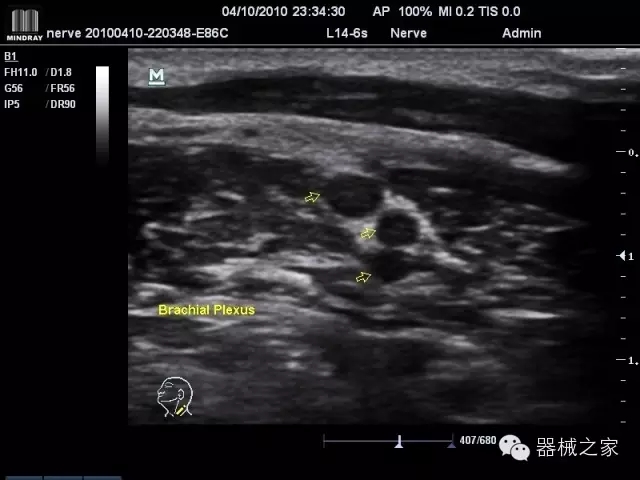

經(jīng)典產(chǎn)品:M7(星鉆)

臨床圖片賞析

產(chǎn)品特點(diǎn)

·裝載有采用Multi-Core多核處理的非嵌入式平臺,成像效率大大提高,并且能夠給用戶帶來高速、多任務(wù)并行信號處理體驗(yàn);

·優(yōu)秀的圖像效果、強(qiáng)大的功能體驗(yàn)、豐富的探頭選擇、合理的便攜式設(shè)計(jì),全中文顯示及病人管理界面,使得M7在任何場合、任何時候都能快速響應(yīng)更好的心血管、腹部、婦產(chǎn)、小器官等常規(guī)超聲檢查以及肌骨、神經(jīng)、顱腦、術(shù)中等新興領(lǐng)域的使用需求;

8倍波束并行處理系統(tǒng)

·在便攜式緊湊平臺上采用更多倍波束并行接收信號處理模式,無論二維還是彩色血流圖像狀態(tài)下,擁有更靈敏的回波頻移捕獲能力,大大提高時間分辨率,尤其使得心血管表現(xiàn)更為突出;

PSHI?寬帶頻移諧波技術(shù)

·在普通組織諧波的基礎(chǔ)上,通過精確控制的波束形成器,發(fā)射兩組具有相位偏差反向的信號,并采用并行信號處理,數(shù)字化合成并采樣回波信號,在高靈敏度的濾波器的處理過程中獲取更純凈的諧波信號,使圖像具有更加出眾的細(xì)節(jié)分辨率;

iClear®+iBeam?

·智能化按線復(fù)合多角度獲取聲束的原始信號,配合智能化的斑點(diǎn)噪聲識別及控制處理技術(shù),整體提高組織結(jié)構(gòu)細(xì)節(jié)分辨率,任何時候都能快速響應(yīng),更好的滿足心血管的使用需求;

支持全新3T工藝探頭群

·包括探頭材料、結(jié)構(gòu)設(shè)計(jì)、加工工藝三方面的革新技術(shù)給圖像帶來品質(zhì)的飛躍;

CFDA注冊證編號

·粵食藥監(jiān)械(準(zhǔn))字20132230475